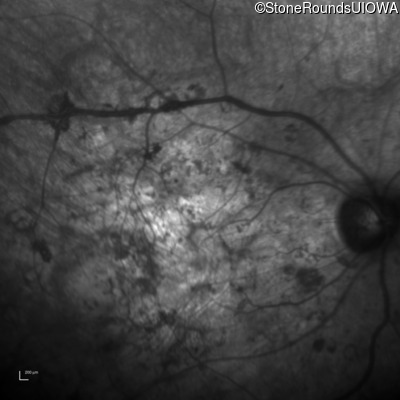

Infrared Fundus Photograph - Right - Hand Motion sc

Exemplar